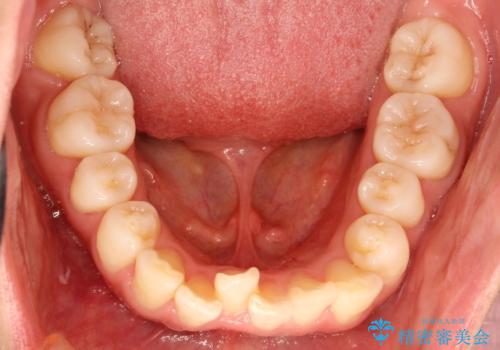

- 上の前歯が出てて、前歯で咬めないとのことで来院されました。

上顎の歯を1本抜歯して、前歯のガタガタと、前方に出ているのを改善する計画としました。

上下の前歯の距離が近くなり、前歯で咬みやすくなり、審美的にも改善できました。